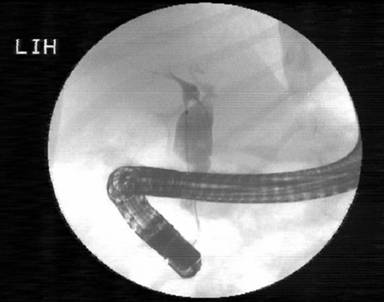

From the second post-ERCP day, her fever started to normalize The amount of bilious drain fluid decreased and, on day 5 after the ERCP, the peritoneal drainage tube was removed. Amylase and lipase levels became normal and, after 7 days, the fever subsided. A repeat ultrasonography 2 weeks later was normal except for mild dilatation of the bile duct. ERCP was carried out 4 weeks later and the stent was removed. A cholangiogram showed a fusiform dilation of the upper two-thirds of the bile duct with no evidence of a leak (Figure 3). The intrahepatic biliary radicles were normal. A repeat MRCP also showed a choledochal cyst (Figure 4). The child has been doing well and surgery for the choledochal cyst is planned for a later date.

Figure 3. Subsequent ERCP showing a choledochal cyst. The stent has been removed. |